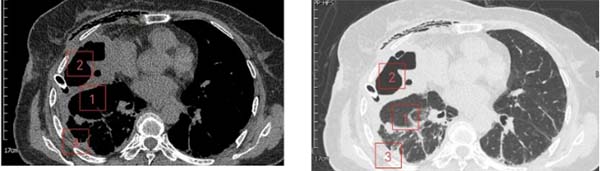

术后1周胸部CT纵膈窗/肺窗

1、肺复张;2、脓腔与肺大疱消失,残留空腔;3、脓胸消失。